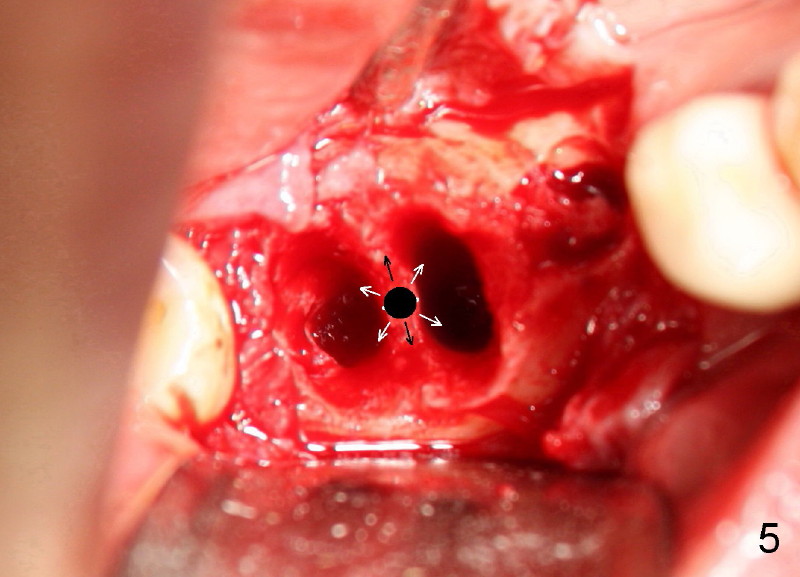

Six weeks post-extraction, a straight incision is made along the crest of #30/31. Without raising flap, #15 surgical blade, bone scalpels (4,5,6 mm wide) and bone blades (4,5.5,7.5 mm wide) ) (Fig.4 white line (illustration); Tatum Surgical) are used to expand the septum buccolingually (arrows). Then round tapered osteotomes (Fig.5 black circle (illustration)) are used to expand the septum circumferentially (arrows). Bone expansion with osteotomes alternates with sequential drills using irrigation. Fig.6 shows 4x17 and 4x14 mm drills placed in sockets #30 and 31, respectively. It appears that osteotomies are placed somewhat distally. The drill #31 is distal to the septum (*).